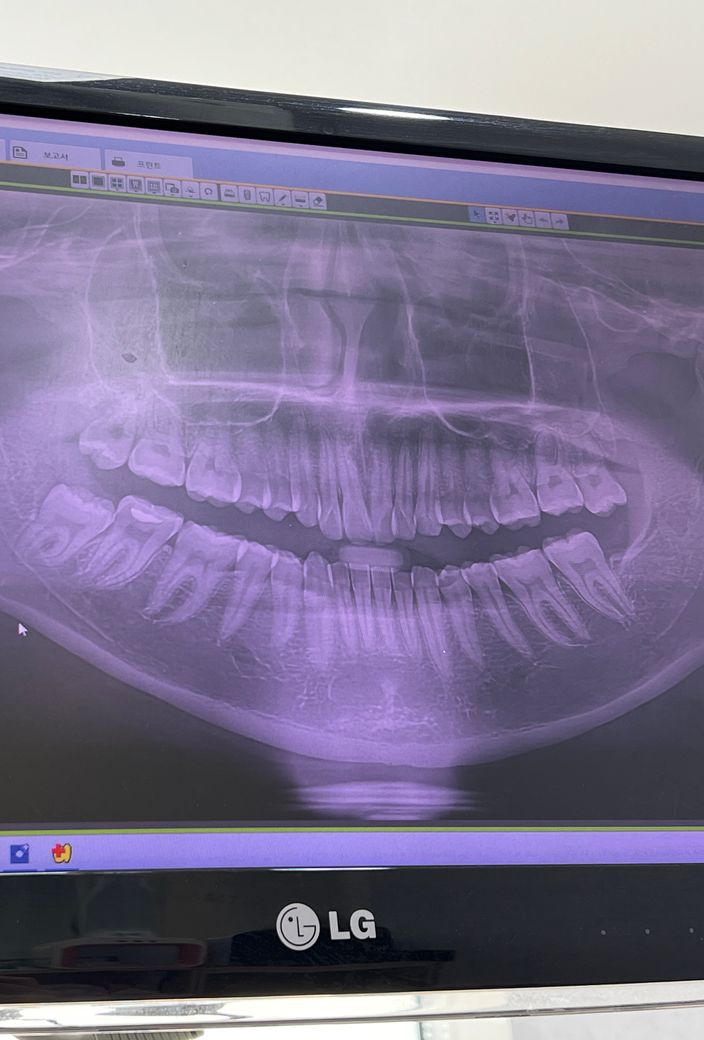

오늘 찍은 엑스레이 사진 올려봅니다 ㅠㅠ

부위는 제기준 오른쪽아래 사진 기준으로 왼쪽아래 사랑니입니다

• 안녕하세요 치과의사 김철진입니다. 사랑니가 신경이랑 겹쳐 보이는거 같습니다 정확한건 CT를 찍어봐야 알겟지만 안전하게 뽑으시려면 대학병원에 가셔서 발치를 하시는게 좋을것같습니다.

2. 오른쪽 아래 사랑니의 경우 이미 뼈에 걸려 맹출은 더 이상 일어나지 않을 것 같습니다.

3. 신경관과 가까운 것은 맞으므로 CT장비가 있는 치과 또는 대학치과병원 내원을 권유드립니다.